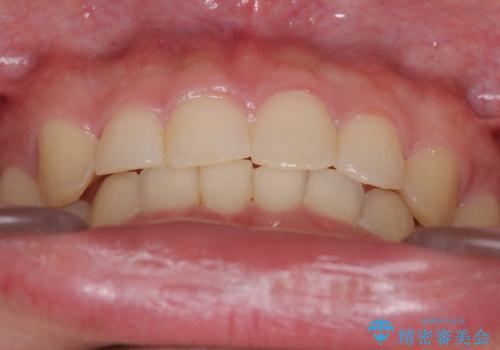

【インビザライン】前歯のガタガタと、前歯の噛み合わせが深いことを治したい。

- 前歯のガタガタと、前歯の噛み合わせが深いことを治したい。との主訴で来院されました。

シミュレーションを用いながら患者様と仕上がりについて相談しインビザラインにて治療を行いました。

仕上げは追加アライナーを数回利用しておこないました。